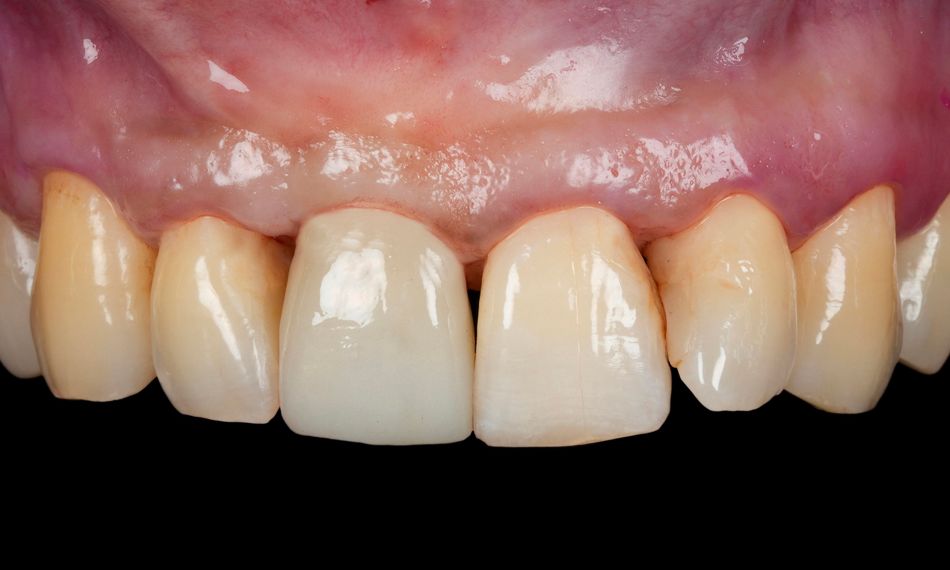

Three months postoperatively, the Maryland bridge was removed. The soft tissue healing was satisfactory (Figs. 22-24).

A screw-retained zirconia provisional crown was delivered. The temporary restorations were milled for optimal fit and esthetics. The provisional was designed in an ideal way based on the digital scan during PI surgery (Figs. 25,26).